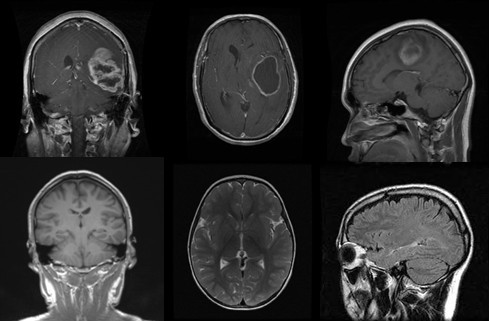

The Brain MRI Dataset comprises T1-weighted contrast-enhanced MRI images of human brains. There are more than 7000 MRI slices, labeled by radiologists, making this dataset more reliable in terms of ground truth. The dataset initially contained four classes (glioma tumor, meningioma tumor, pituitary tumor, and no tumor), which were then converted into just two classes (tumor and no tumor), as shown in the Figure 1.

Refer to caption

Figure 1: Sample images from the Brain MRI dataset showing tumor, and no tumor cases.